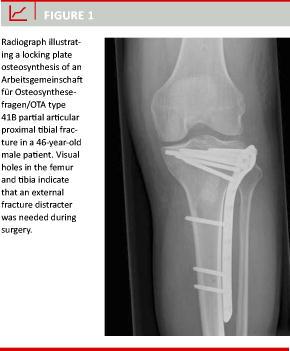

All patients were managed in accordance with the department’s protocol for proximal tibia fractures which includes prophylactic antibiotics and postoperative low-molecular-weight heparin. With the patient in a supine position, under C-arm guidance and, when needed, with the use of an external fracture distracter, reduction of the articular surface was achieved through the fracture gap or through a small cortical window osteotomy distal to the fracture. The plate (LCP Proximal Tibial Plate 4.5/5.0 lateral, Synthes, Solothurs, Switzerland or OptiLock Periarticular Plating System, Proximal Tibial Plate Application, Biomet, Parsippany, NJ, USA) was inserted through a curved anterolateral incision and additional stab-incisions were made for the distal screws (Figure 1). The plan for postoperative weight-bearing and hospital discharge was given individually by the surgeon.